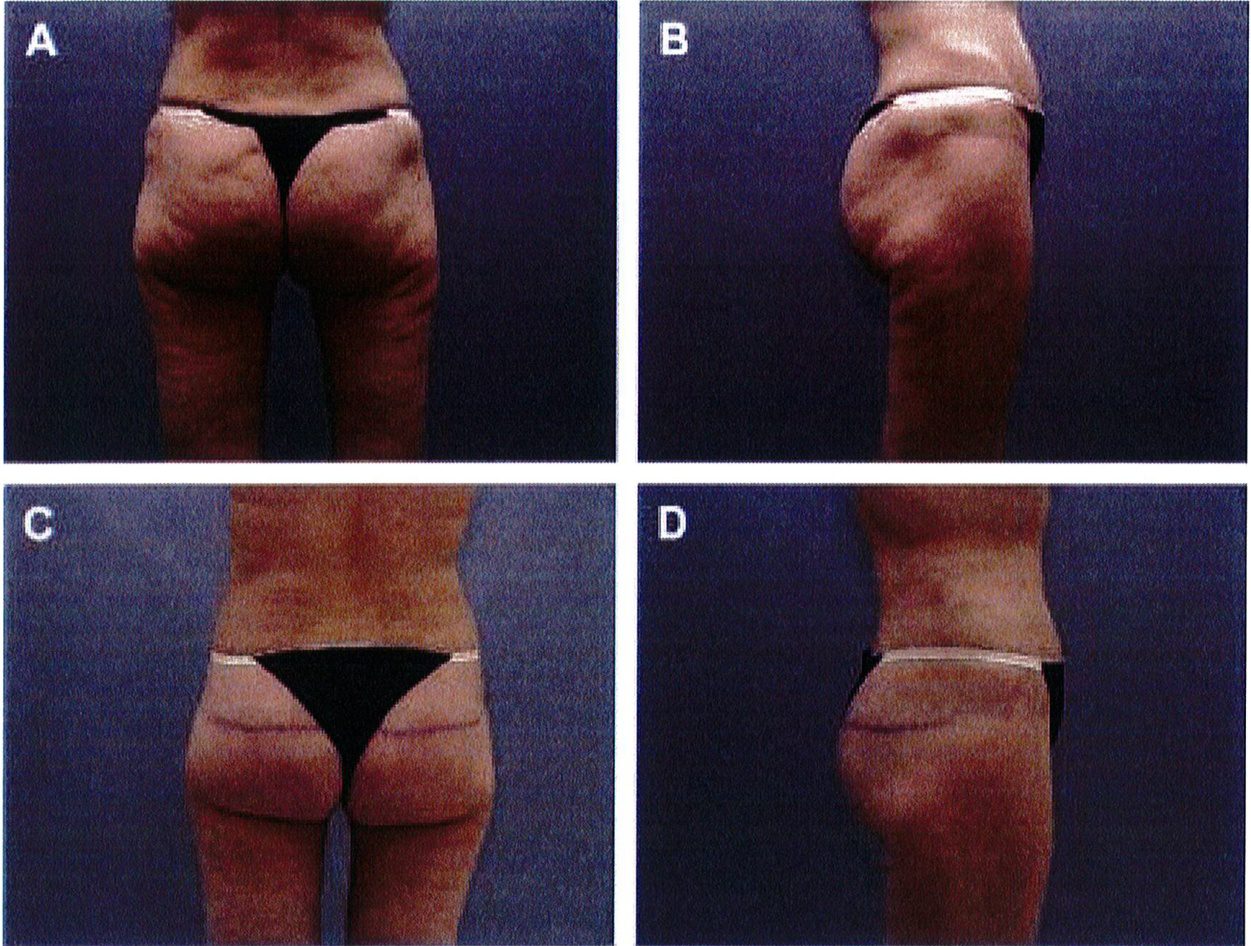

Hình. 12. (A, B) Bệnh nhân nữ 37 tuổi với vùng mông dẹt và xệ. (C,D) Tám tháng sau phẫu thuật tạo hình thành bụng và tạo hình mông bằng phương pháp purse- string .